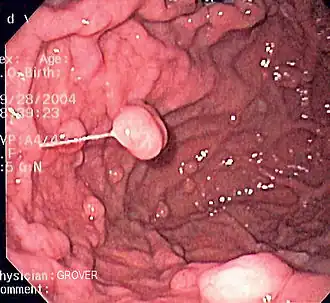

Гастроинтестинальная эндоскопия

Эндоскопические исследования выполняются с помощью специальных аппаратов-эндоскопов, вводимых пациенту через естественные отверстия — рот или задний проход и передающих изображение в исследуемом органе или на окуляр эндоскопа или на монитор. В современной практике используются два типа гибких эндоскопов: волоконно-оптические фиброэндоскопы и видеоэндоскопы, оцифровывающие видимую в объектив картинку и передающие её в таком виде на монитор или окуляр. Эзофаго-, гастро-, дуодено- и/или еюноскопия показаны при подозрении на воспаление или язву, а также другие заболевания пищевода, желудка, тонкой кишки, фатерова сосочка. Колоноскопия — эндоскопическое исследование толстой кишки, показана при наличии клинических признаков, указывающих на поражение толстой кишки, наблюдении за пациентом в процессе лечения, при осмотрах, направленных на выявление на ранней стадии онкологических и других заболеваний[22].

- Эндоскопические исследования пищевода, желудка и кишечника

-

Гибкий волоконно-оптический фиброэндоскоп -

Эндоскопия пищевода пациента с варикозным расширением вен пищевода -

Полипы фундальных желёз желудка. Изображение получено с помощью фиброгастроскопа -

Дуоденоскопия пациента с аденокарциномой двенадцатиперстной кишки